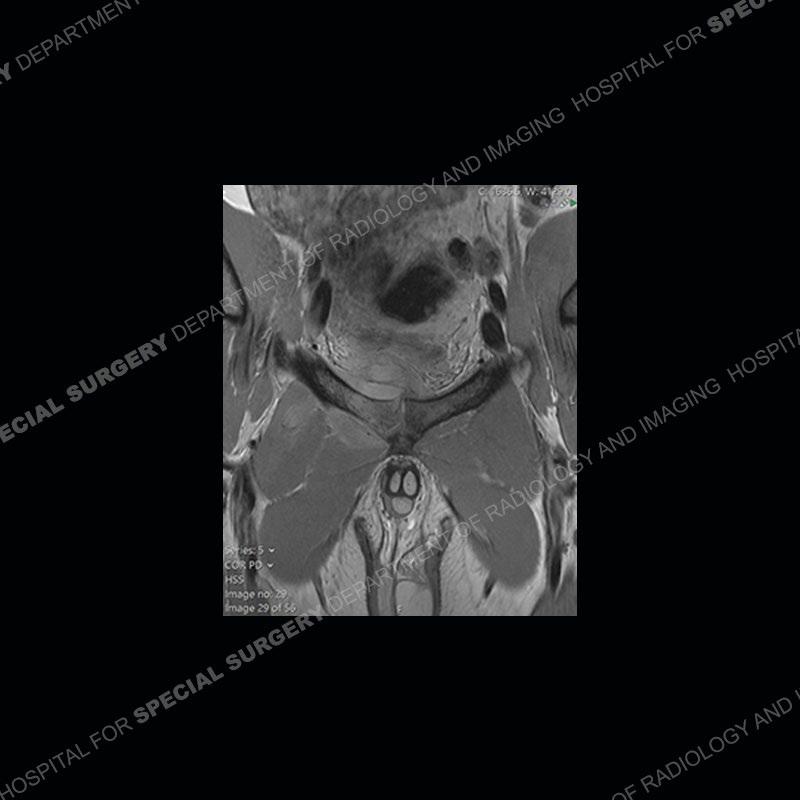

Radiographs did not demonstrate any clear abnormality. The MRI shows markedly abnormal signal of the right superior pubic ramus and abnormal signal/”mass” extending into the adjacent soft tissue. The inferior articular surface of the ramus showed what was thought to be bony destruction. CT examination shows a destructive process of the right superior pubic ramus.

Subsequent MRI in a very short time interval shows markedly increased abnormality of the ramus and increased edema and “mass” of the soft tissue. Post contrast imaging shows multiple, rim enhancing collections of the soft tissue and similar albeit less conspicuous enhancing collection of the ramus.

Diagnosis: Osteomyelitis and Soft Tissue Abscess